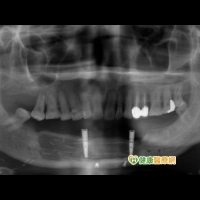

一名48歲中年男子,下顎前牙區罹患口腔癌,手術時以小腿骨及皮瓣重建被切除的下顎骨,經過多次手術,下顎缺牙區恢復軟硬組織形態後,以人工植體覆蓋式義齒重建口腔功能。

范姜如君表示,罹患口腔癌的患者,在手術後常面臨美觀與口腔功能受限的困擾,而人工植牙技術可應用於口癌症患者的術後口腔重建,幫助提升病患的咀嚼與說話功能改善術後生活品質。